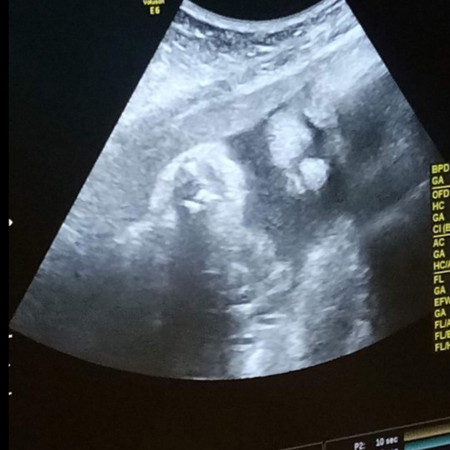

บ้านนี้กำหนดคลอด24พค ค่ะ แต่หมอนัดต้นเดือนค่ะ

กำหนด26 พค. ลูกสาวเหมือนกันจ้า

5 พ.ค.ได้ลูกสาวเหมือนกันจ้า

8พ.ค.ลูกชายอีกคนค่ะบ้านนี้

21 พ.ค. ได้ลูกชายค่ะ

16 พ.ค ลูกชายยจ้า